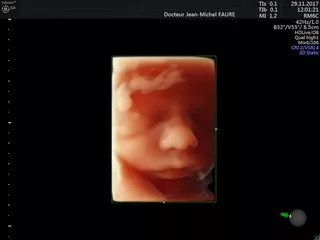

Jean-Michel FAURE

Dr Faure

Tous les examens échographiques sont réalisés avec les échographes les plus récents du marché, mis à jour régulièrement, et sont conformes aux recommandations de bonnes pratiques des sociétés françaises :